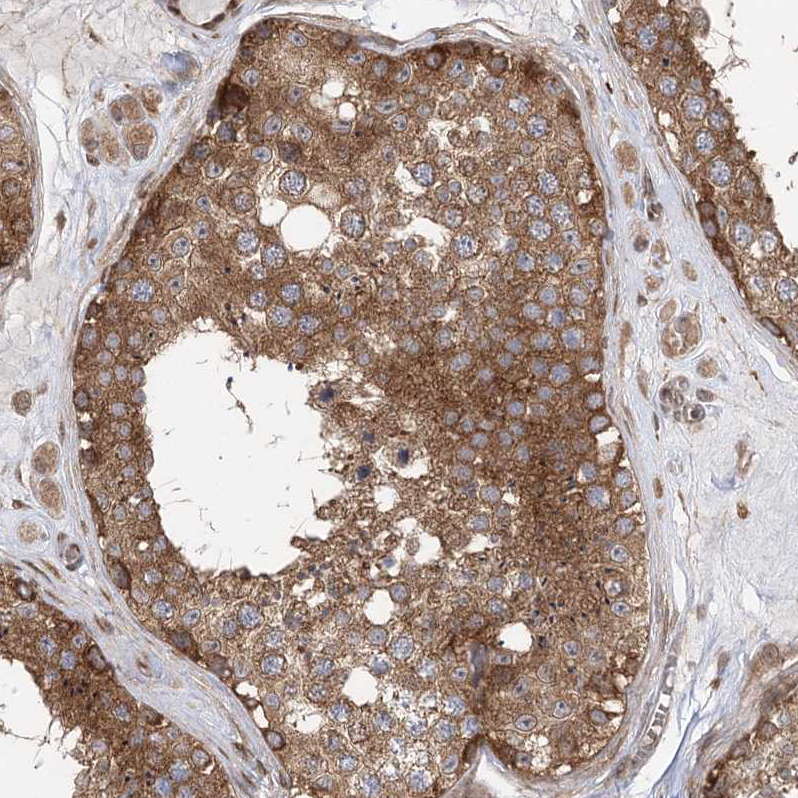

Immunohistochemical staining of human testis shows strong cytoplasmic positivity in cells in seminiferous ducts.